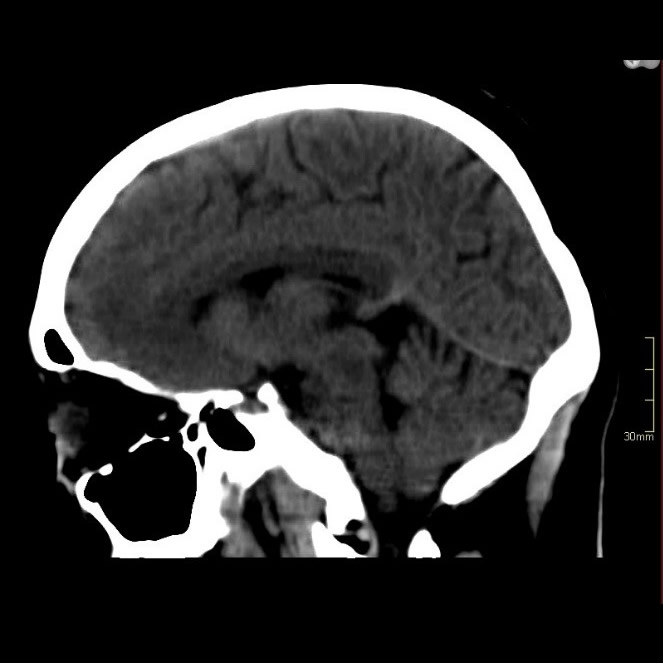

Abril 2019. Hospital Privado Paciente femenina de 35 años que consulta por mareos y diplopía. APP: hepatitis autoinmune (hace 11 años).